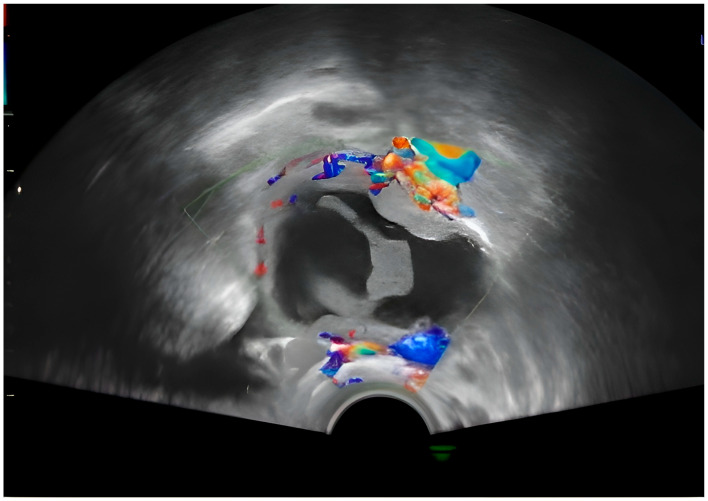

背景:息肉样子宫内膜异位症是一种罕见的子宫内膜异位症,表现为肿瘤肿块,很难与恶性肿瘤区分。它通常发生在围绝经期妇女或接受激素治疗的妇女中,在年轻孕妇中出现极为罕见。病例介绍:这篇文章描述了一个罕见的妊娠妇女的息肉样卵巢子宫内膜异位症,在医学文献中很少有记录的病例。在常规产前超声检查中偶然发现附件肿块,其影像学特征引起了肿瘤过程的怀疑,并提示手术排除恶性肿瘤。然而,切除病变的组织病理学检查证实了与息肉样子宫内膜异位症相符的特征,没有发现癌症的证据。本病例强调了鉴别子宫内膜异位症与卵巢肿瘤的诊断挑战,特别是在妊娠期间,影像学表现可能不明确。此外,妊娠期固有的激素环境可能加剧子宫内膜异位症病变的增殖行为,从而使临床评估复杂化。在这种情况下,附件肿块的存在通常需要仔细评估,以平衡手术风险和延迟诊断的潜在后果。提出的数据强调了准确诊断的重要性。最后,协调良好的做法可确保保护孕产妇和胎儿健康。结论:通过优先准确的诊断和个性化的治疗方案,医生可以最大限度地减少并发症,改善母亲和孩子的预后。

Background: Polypoid endometriosis is a rare variant of endometriosis that presents as a tumorous mass, making it difficult to differentiate it from a malignant tumor. It usually occurs in perimenopausal women or those undergoing hormone therapy, and its presence in a young pregnant woman is extremely uncommon. Case Presentation: This article describes a rare instance of polypoid ovarian endometriosis in a pregnant woman, a condition with few documented cases in the medical literature. An adnexal mass was discovered incidentally during a routine prenatal ultrasound, with imaging features that raised the suspicion of a neoplastic process and prompted surgery to exclude malignancy. However, histopathological examination of the excised lesion confirmed features compatible with polypoid endometriosis, without revealing evidence of cancer. This case highlights the diagnostic challenges of differentiating polypoid endometriosis from ovarian neoplasms, especially during gestation, where imaging findings can be ambiguous. In addition, the hormonal environment inherent in pregnancy may exacerbate the proliferative behavior of endometriotic lesions, thus complicating clinical evaluations. The presence of an adnexal mass in such a setting often requires careful evaluation to balance the risks of surgery with the potential consequences of delayed diagnosis. The data presented emphasize the importance of an accurate diagnosis. In conclusion, a well-coordinated approach ensures the protection of maternal and fetal health. Conclusions: By prioritizing accurate diagnosis and personalized treatment plans, physicians can minimize complications and improve outcomes for both mother and child.